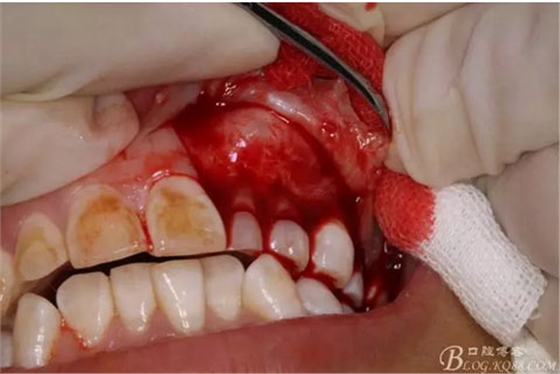

圖9.從兩個(gè)切口的連接處開(kāi)始翻瓣。全厚瓣。

圖10.暴露出骨性隆起。骨質(zhì)表面光滑。

圖11.暴露出23的牙尖,牙尖垂直于唇側(cè)粘膜。建議拔除,患者同意。

圖12.用小骨鑿去除覆蓋在牙瘤表面的骨質(zhì)。發(fā)現(xiàn)牙瘤的包膜。